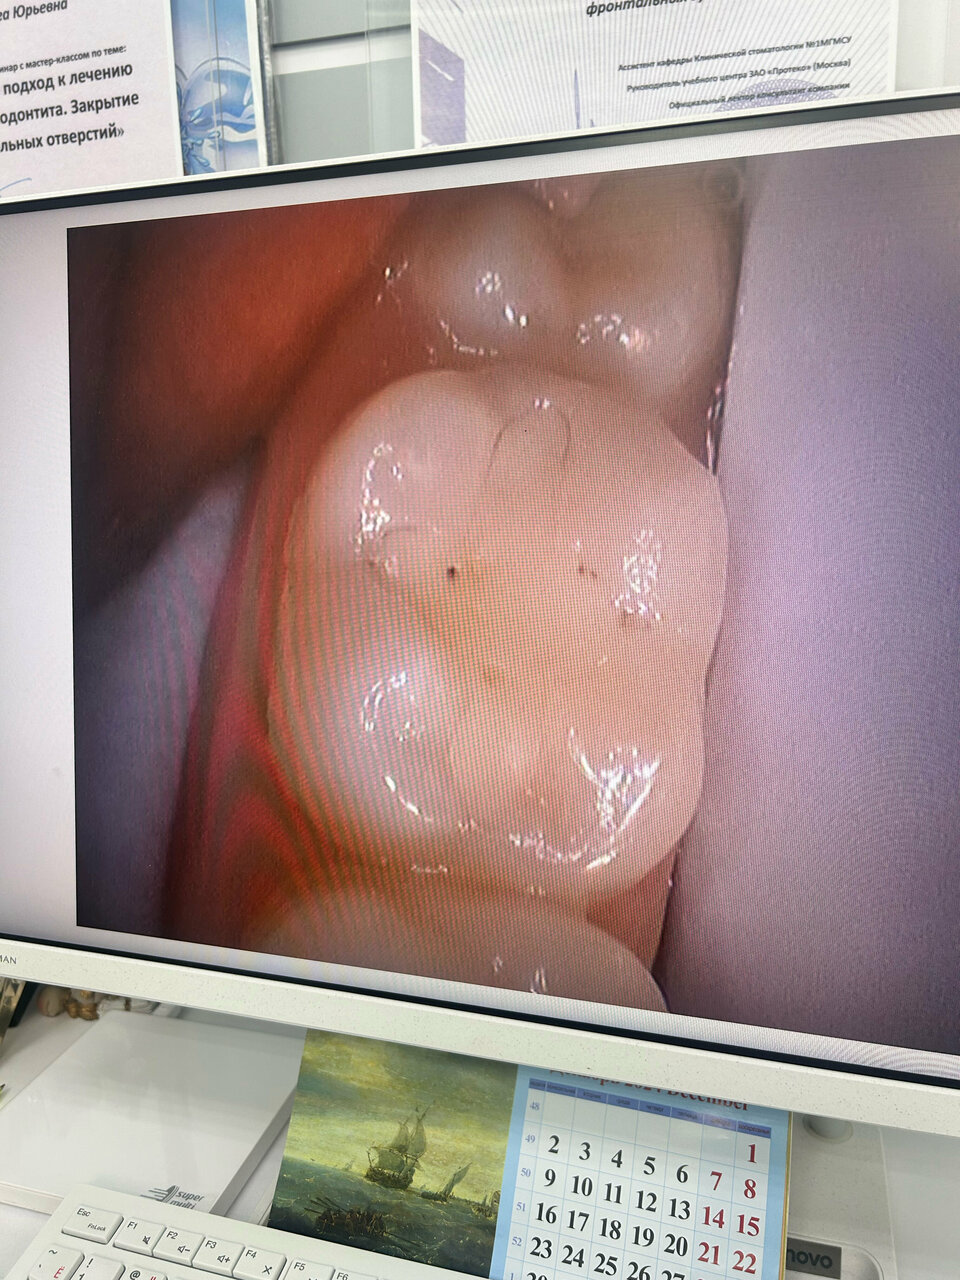

Сотрудничаю с этой клиникой с 2006 года и не разу не сожалела об этом!!! Лучшие специалисты Юрьевна Ольга Юрьевна, врач-терапевт красивая женщина и профессионал с большой буквы. Стоматолог-ортопед Артюхов Александр Владимирович, лучшее протезирование в городе!!!! Точность, аккуратность, профессионализм и замечательная улыбка. Здесь всегда рады помочь. Спасибо вам большое.

Много лет всей семьей лечимся у Юрьевой О.Ю. По нашей рекомендации даже друзья приезжают именно к ней с другого конца города. Ольга Юрьевна настоящий профессионал! Персонал клиники вежливый и отзывчивый. Всегда только приятные впечатления от посещения. + часто бывают интересные акции и скидки на услуги, есть бонусная программа.

Космостом — супер!!! Всегда рекомендую! Мы вместе уже почти 20 лет. Лечение,протезирование- на высшем профессиональном уровне. Каждый год приглашают на осмотр .С удовольствием приезжаю к Юрьевой Ольге Юрьевне! Это высококлассный специалист и просто добрая, милая женщина! Всем счастья и здоровья!

Замечательная стоматология, отдельное спасибо Ольге Юрьевне, отличный специалист

Более 10 лет лечусь в клинике Космостом у Юрьевой Ольги Юрьевны! Огромная благодарность доктору за доброту, заботу, тактичность и аккуратность!